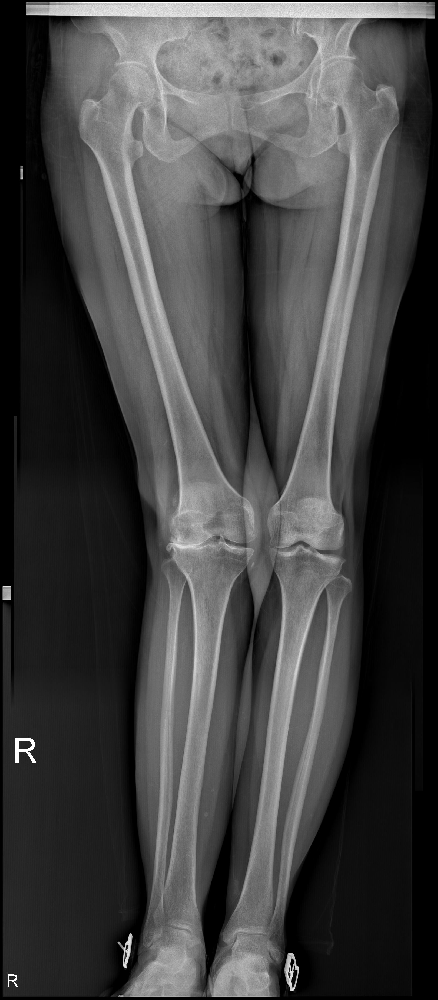

10年前,賈知梅的右膝關(guān)節(jié)開始疼痛,并伴隨著獨(dú)特的外翻畸形。這種痛苦持續(xù)了10年,時斷時續(xù),隨著勞累的增加而加劇。只有休息,她才能稍稍得到緩解;負(fù)重時,疼痛則變得更加明顯。為了緩解這種癥狀,賈知梅曾前往當(dāng)?shù)氐脑\所接受了針灸、按摩理療,效果也令她稍為舒服一些。

然而,一年前,賈知梅的右膝關(guān)節(jié)疼痛再度加重,甚至使她失去了行走的能力。在疼痛急劇惡化時,她只能依靠口服止痛藥稍稍緩解一些痛楚。面對這樣的困境,賈知梅選擇了市中區(qū)誠德骨科醫(yī)院入院,并接受了一項(xiàng)名為右膝外側(cè)固定平臺單髁置換術(shù)的手術(shù)。